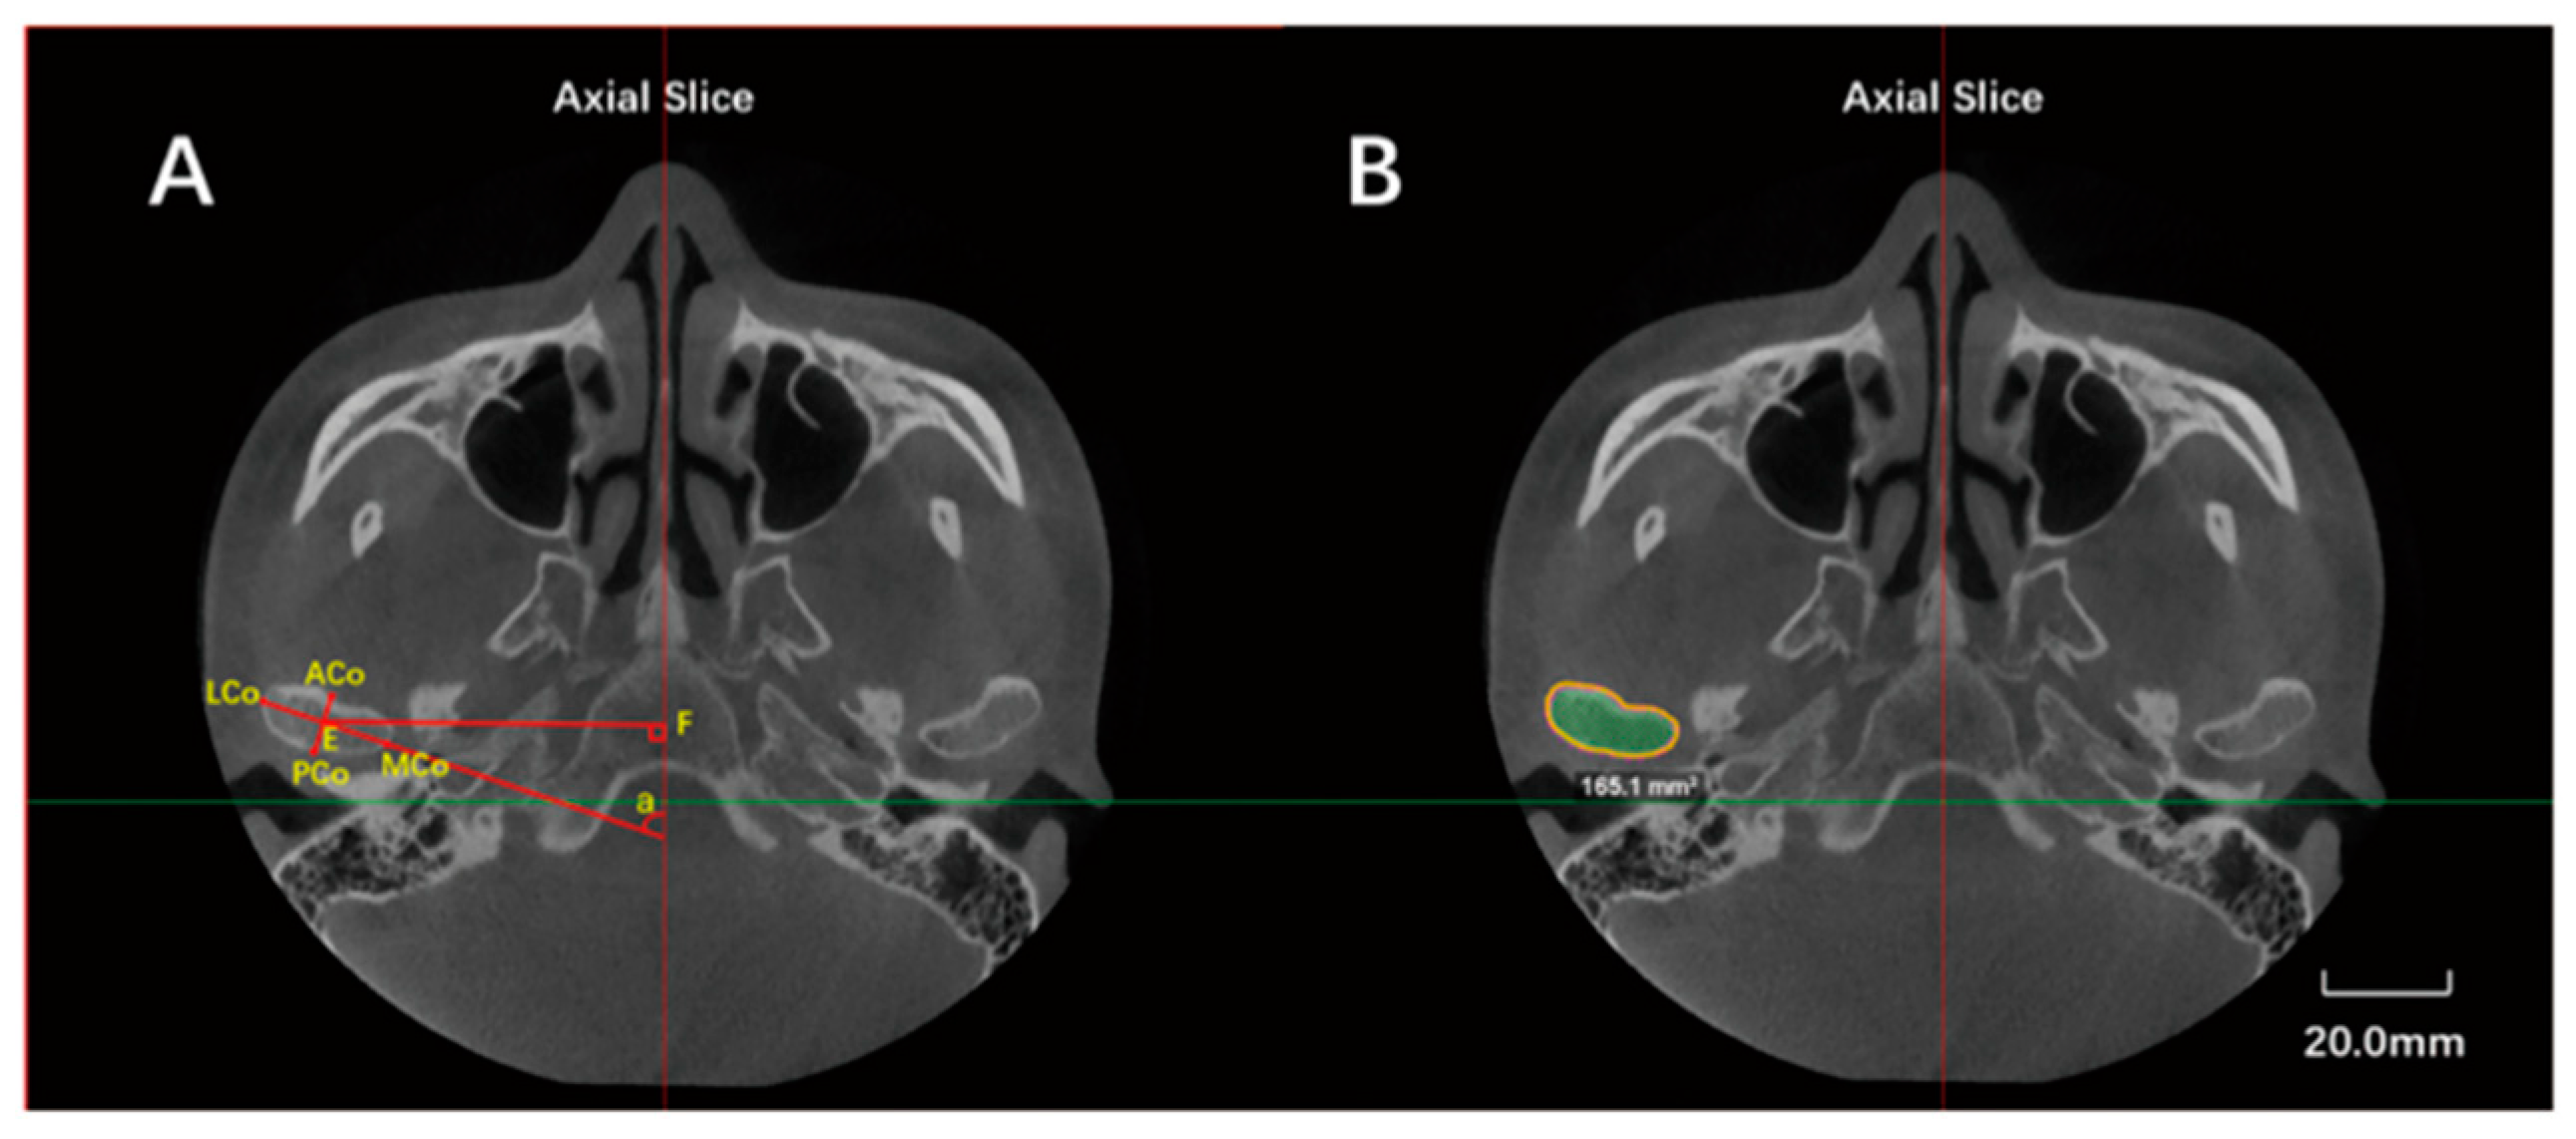

| Landmarks, Constructed Lines and Measurement Items | Abbreviation | Definition |

|---|---|---|

| Lateral condylar point | LCo | Most lateral point of the condyle |

| Medial condylar point | MCo | Most medial point of the condyle |

| Anterior condylar point | ACo | Most anterior point of the condyle |

| Posterior condylar point | PCo | Most posterior point of the condyle on axial plane |

| Anteroposterior diameter | ACo-PCo | Distance from ACo to PCo |

| Transverse diameter | LCo-MCo | Distance from LCO to MCo |

| Maximal sectional area | Smax | Maximal sectional area of the condyle |

| Axial angle | - | Angle between LCo-MCo and midsagittal line |